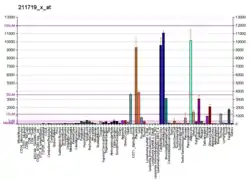

- ↑ Chicco D, Alameer A, Rahmati S, Jurman G (November 3, 2022). "Towards a potential pan-cancer prognostic signature for gene expression based on probesets and ensemble machine learning". BioData Mining. 15 (1): 28. doi:10.1186/s13040-022-00312-y. eISSN 1756-0381. PMC 9632055. PMID 36329531.